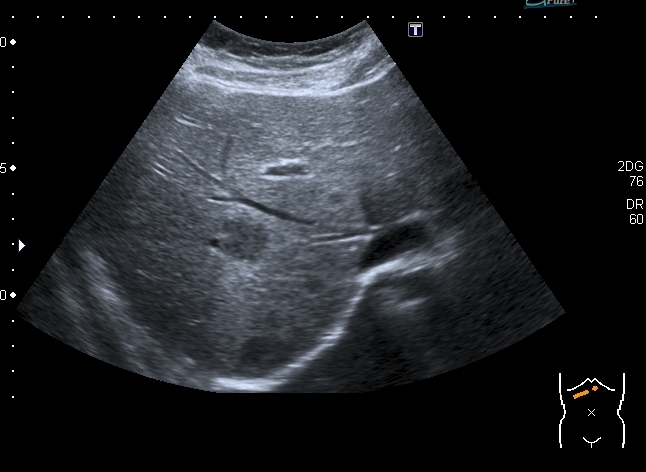

Девочка 13 лет, в течение 2-х недель температура до 38, СОЭ - 40 мм\ч, СРБ - 30.

На УЗИ: Учитывая клинику, лабораторные данные поставил гистиоцитарную инфильтрацию печени и селезёнки при генерализованной инфекции. Несколько раз встречался со схожими случаями, на фоне антибиотикотерапии изменения уходили. Но в данном случае девочка уже получала антибиотики в течение недели, на этом фоне не получено ни клинического , ни лабораторного улучшения, а на УЗИ очаги стали больше. Нужно ли расширять дифференциально -диагностический ряд? Ваши мнения

Имхо, по УЗ-семиотике - множественные небольшие абсцессы.

Из -за того , как назвать данные изменения у нас в больнице постоянно возникают споры между педиатрами и хирургами, а крайние - мы. Если мы в своём заключении упомянём слово "абсцесс" - девочку сразу же переведут в хирургическое отделение: абсцесс= гной, где гной - там разрез. Весь вопрос в том , что гноя в этих очагах нет и хирурги категорически отказываются участвовать в лечении данного заболевания, скорее это инфильтраты, или по лекции С. И. Пиманова - гистиоцитоз печени и селезёнки. Упомянув данное слово , мы ввергаем педиатров в панику, т. к. у них возникает ассоциация с гистиоцитозом X, хотя это несолько из другой оперы.KapustinSV писал(а):Имхо, по УЗ-семиотике - множественные небольшие абсцессы.

Есть мысль о КТ с контрастированием , думаю в данных очагах накопление контраста должно отличаться от очаговых поражениях при лимфомах.